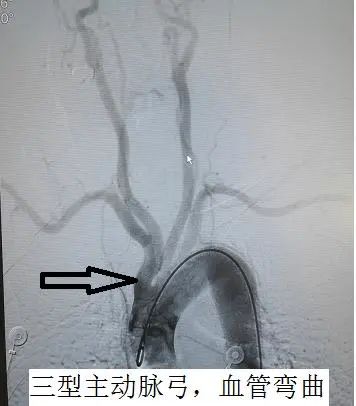

神经外科二组主任王宝庆带领副主任医师郭知伟和住院医师王尧迅速为患者做了脑血管造影,DSA检查结果显示:颅内动脉瘤(右侧颈内动脉交通段动脉瘤,与头部CT显示出血吻合)。病因明确了,动脉瘤破裂出血是本次发病的罪魁祸首。但是患者脑部血管为典型的“三型弓”,介入治疗动脉瘤导管到位十分困难,但考虑到脑动脉瘤的危害,如果第二次破裂出血的死亡率达到50%以上,患者将随时面临死亡的危险,会引起脑积水、脑出血等并发症。王宝庆主任根据病人特点与患者家属充分沟通,建议手术治疗,言简意赅地介绍了介入和开刀两种手术方式的利弊,最终家属选择开颅夹闭动脉瘤。